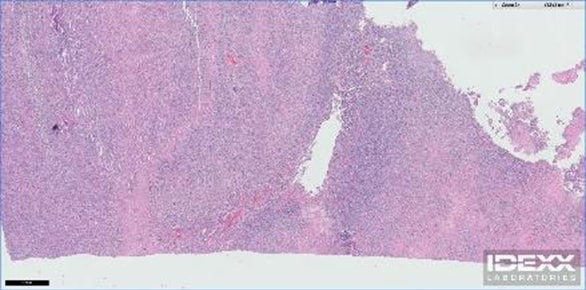

Microscopic disease is the level of cellular change that can't be seen with the naked eye. That is, the disease can be visualized on a slide under the microscope but can't otherwise be readily detected. With cancer, microscopic disease occurs all the time, as cells having abnormal DNA divide rapidly without the proper mechanism to turn off their division. It's takes days to months for enough cancer cells to divide to create a tumor that can then be discovered through physical examination, diagnostic testing, or through the development of clinical signs of illness. As a result, even though your veterinarian may not be able to find cancer in your pet at a particular time, the potential exists that cancer cells that ultimately will form tumors are existing in the body. An image of Cardiff’s microscopic disease as seen on the biopsy of his intestinal tumor is provided courtesy of Idexx Laboratories and is included at the end of this column. What is Macroscopic Disease? Macroscopic disease is that which your veterinarian can discover on a physical examination or via diagnostic techniques like radiographs (x-rays), ultrasound, CT, or MRI. As Cardiff’s cancer returned 12 months after completing his first course of chemotherapy in July 2014, either his chemotherapy didn't kill all of the cancer cells (microscopic disease) or he is just prone to forming cells containing abnormal DNA that then divided without stopping and ultimately formed a tumor. The second option is most likely, as he had such a long disease-free interval, especially considering the poor prognosis that goes with T-Cell Lymphoma. As development of macroscopic disease can happen so fast in some patients, it’s crucial to follow your veterinarian’s guidelines for rechecks, which normally include physical examination, and diagnostics like blood and urine testing, radiographs, ultrasound, and others tests. Cardiff had been getting blood testing every one to four weeks and chest radiographs and abdominal ultrasound every three to four months. Yet, the development of a new intestinal mass occurred and wasn’t seen in the short period of one month between his prior ultrasound in June 2015 and the most recent ultrasound in July 2015. When Cardiff was again diagnosed with an intestinal mass, we were able to visualize his macroscopic disease via ultrasound. Cardiff’s surgeon, Dr. Justin Greco of ACCESS LA, was able to both see and feel the mass during the exploratory abdominal surgery. When it comes to treating macroscopic disease, surgically removing it is most ideal for the patient, provided the patient is healthy enough to endure the anesthesia and surgery. “A chance to cut is a chance to cure” rings true and can alleviate clinical signs of disease or potentially change the course of treatment in a favorable way, such as putting the patient into remission and reducing the need for chemotherapy or radiation to treat residual disease. Removing only a section of a tumor from the body via surgery is still helpful, but leaving behind cancer cells increases the need for chemotherapy and radiation to manage the residual disease. An image of Cardiff’s macroscopic disease, as seen after his intestinal tumor was removed, is also included at the end of this article.What Does This Mean for Cardiff?

Even though Cardiff had surgery which completely removed his intestinal tumor with wide margins, there's still a chance that he has microscopic disease lurking elsewhere in his body. I feel confident that surgery resolved Cardiff’s macroscopic disease, but Cardiff’s veterinary oncologist, Dr. Avenelle Turner, and I still feel that it's best to put him through a course of chemotherapy to kill any microscopic a disease. Doing so will decrease the likelihood that he’ll develop further microscopic and macroscopic disease in the future. Check back next time as I discuss Cardiff’s chemotherapy plan and give an update on his status.Microscopic visualization of Cardiff’s T-Cell Lymphoma courtesy of Idexx Laboratories.